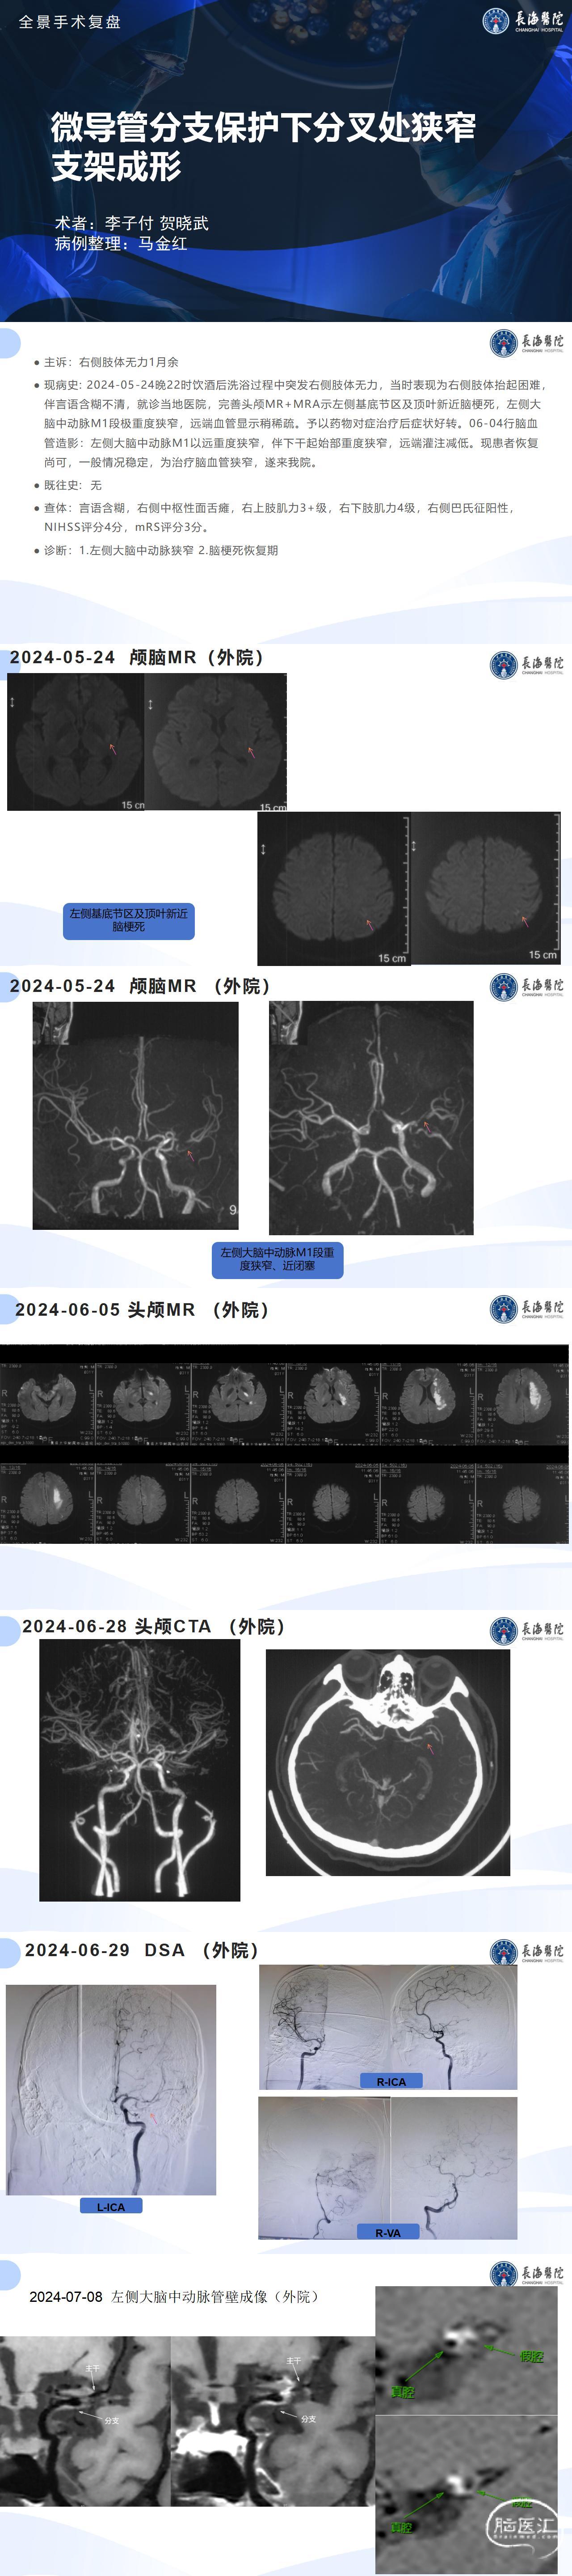

微导管分支保护下分叉处狭窄支架成形